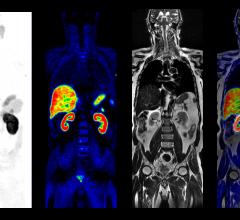

May 9, 2016 — A recent study combined two related but different imaging techniques to non-invasively track the rate at ...

In the world of molecular imaging, PET/MR is a wild card. But it’s a wild card that’s ready to be played. Three major ...